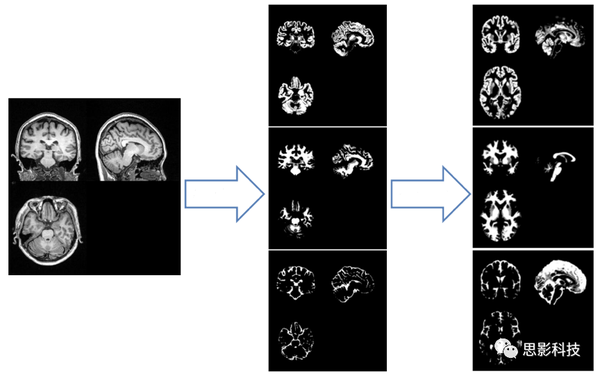

灰质总体积,白质总体积,颅内总体积,灰质总体积/颅内总体积比值,白质

脑结构一般指大脑的灰质,白质以及脑脊液等等,科学研究主要集中在在

matter)和灰质(gray matter)的密度:灰质密度高于白质正常灰白质难以